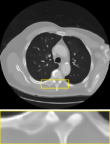

CT We evaluate on computed tomography with Gaussian noise, modeled as , where is the Radon transform. The acquisition uses 51 angles, i.e., about of the LIDC-IDRI image width, with as in training. Results are reported in the rightmost column of Table 2 and visuals in Figure 8. DPIR results are omitted due to instability on this task. The proposed RAM model produces reconstructions with finer details than uDPIR-tied.

CT

We provide in Figure 8 visual results for computed tomography for the in-distribution setup on the top row (i.e., with a setup similar to that of training), and the out-of-distribution setup on the bottom row. In the latter case, measurements are degraded with additional Poisson noise, unlike the training setup.

| uDPIR tied | RAM | Ground-truth | ||

| 0.607 | 0.642 | SSIM | ||

| Poisson CT | ![]() |

| 0.828 | 0.671 | SSIM |